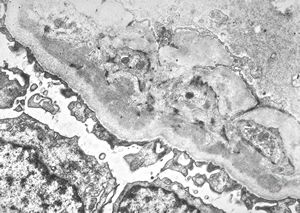

F,14y. | Alport syndrome - split and laminated, thick/thin basement membranes